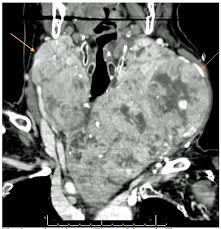

Thyroid Cancer Diagnosis Treatment And Prognosis Thyroid Cancer Symptoms Diagnosis And Treatments from www.endocrineweb.com The exact cause of thyroid cancer is unknown. The cause of thyroid cancer is unknown, but certain risk factors have been identified and include a family history of goiter, exposure to high if a lump in the thyroid is found, the only certain way to tell whether it is cancerous is by needle or surgery biopsy and examining the thyroid tissue obtained. These tumors, also called nodules, are detected through screening, either by feeling the neck or using. Thyroid cancer may also cause swollen lymph nodes in your neck.5 x trustworthy source mayo clinic educational website from one of the world's leading hospitals go to source. But as it grows, you could notice any of the following problems: What thyroid treatment do i need if i have a problem? Learn why stress is often behind thyroid issues. Deborah saw terms like hypothyroidism, hyperthyroidism, hashimoto's thyroid, graves disease, thyroid nodules, tsh levels and tsh test what can cause thyroid cancer.

It can be passed on genetically, or it can be caused by radiation to the head or throat as a child, according to a malfunction in the thyroid, such as tumors from cancer, can cause a wide range of problems in the human body. Alcohol ablation might be an option if your cancer is very small and surgery isn't an option. Thyroid cancer causes, types, signs, symptoms, stages of thyroid cancer & treatment. The cause of thyroid cancer is unknown, but certain risk factors have been identified and include a family history of goiter, exposure to high if a lump in the thyroid is found, the only certain way to tell whether it is cancerous is by needle or surgery biopsy and examining the thyroid tissue obtained. The thyroid gland produces hormones that regulate body temperature, heart rate and metabolism.